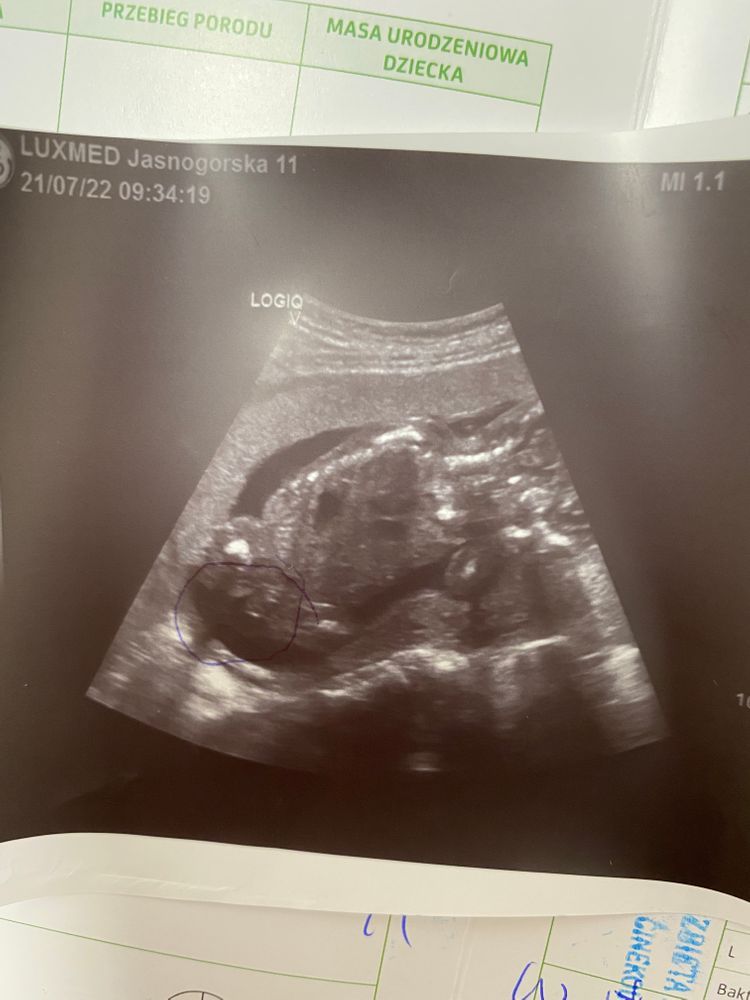

Нана, естественно после этого поста начала искать что то похожее,нашла как узист объясняет тоже на таком примере,что мальчик, и где писюн. Я конечно тоже сначала поверила узисту,но вот тот пост заставил сомневаться Изображение

07.12.2024

Нана, а,и врачи плохо посмотрел,т к малыш очень активный и стоило только найти вот половой орган,малыш шевелился и все сбивалось